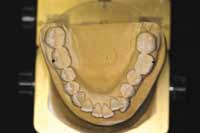

Figure 15 Removable retention that was used for 6 months.

Figure 16 Final upper and lower waxup, maintaining the established position. The temporary stent was made from the waxup.